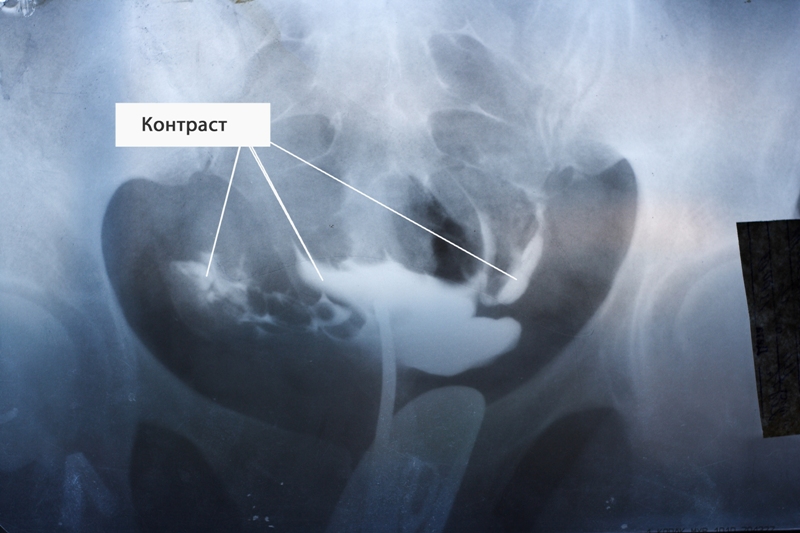

Гистеросальпингографией (ГСГ) или метросальпингографией (МСГ) называется диагностическое исследование проходимости фаллопиевых труб и изучение их состояния. Этот метод представляет собой проведение рентгена с дополнительными манипуляциями. Процедуру выполняют сразу два врача: рентгенолог и гинеколог. Врач вводит в полость матки катетер, через него поступает контрастное вещество. Способность вещества проникнуть через трубы в брюшную полость говорит о степени их проходимости.

Основное преимущество гистеросальпинографии — высокая информативность, так как контрастная жидкость четко видна на снимках. К тому же после процедуры у пациентки они на руках остаются снимки, с которыми можно обратиться к другому специалисту в любое время.

Как правило, за время проведения процедуры делают от 4 до 6 снимков. Вначале фиксируется состояние матки. Затем в полость подают еще 4 мл контрастного вещества, что позволяет более четко осмотреть придатки. Если этого объема жидкости недостаточно, то вводят столько, сколько необходимо. После того как жидкость заполнит орган, она устремляется в трубы. Если на изображении видно, что раствор вышел в брюшную полость с обеих сторон, то трубы проходимы. Если же нет, то можно увидеть, на каком участке жидкость остановилась.

Для проведения процедуры используют контрастную жидкость, которая имеет способность задерживать рентгенологические лучи.